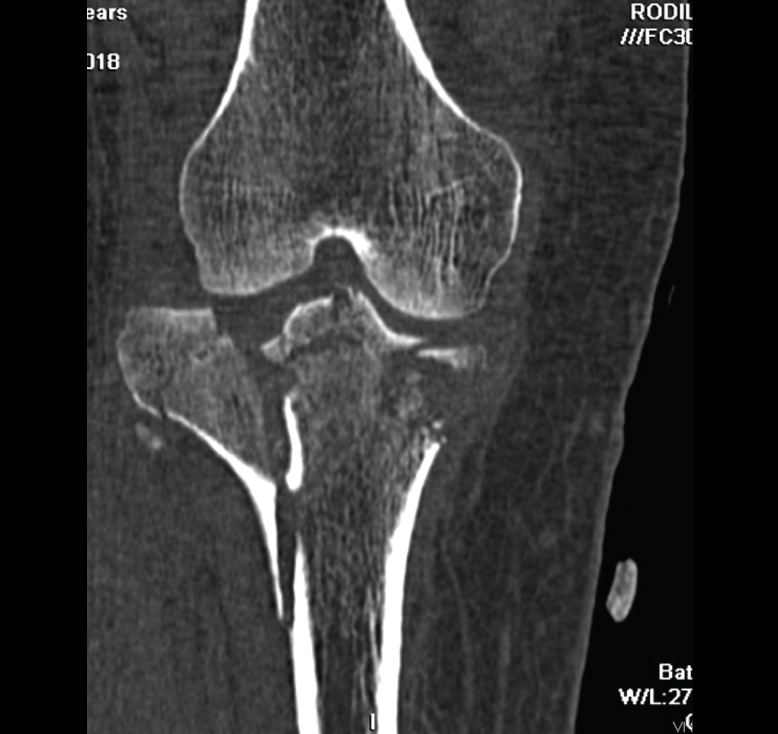

1.2. Tibia (Figura 20)

Figura 20. Corte de reconstrucción coronal de tomografía axial computarizada de rodilla: fractura de ambas mesetas tibiales.